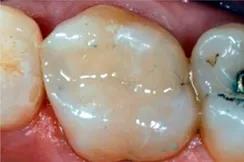

去腐备洞

去腐备洞:打开窝洞可以清晰的看到邻面龋坏的程度,和龋齿探测仪中所检查的龋坏窝洞范围及形态基本一致。

充填

窝洞充填:使用kerr光固化树脂进行窝洞充填。